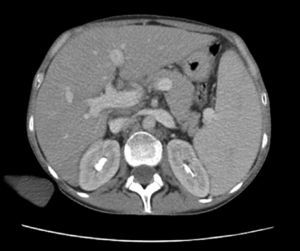

Cultures of blood, urine, stool and bone marrow were negative for common bacteria, typical and atypical mycobacteria and fungi. Thoracentesis reported an uncomplicated exudate. Computed tomography with contrast (oral and IV) of the head, neck and pelvis were normal; the scan showed the presence of a bibasal pleural effusion, and the abdomen (Fig. 1) showed homogeneous hepatomegaly (230mm of longitudinal diameter) and splenomegaly (200mm of longitudinal diameter). Hepatic vessels on an eco Doppler ultrasound showed dilation of the portal vein (14mm in diameter) with no evidence of thrombosis. Upper gastrointestinal fiberoptic endoscopy ruled out the presence of esophageal varices.